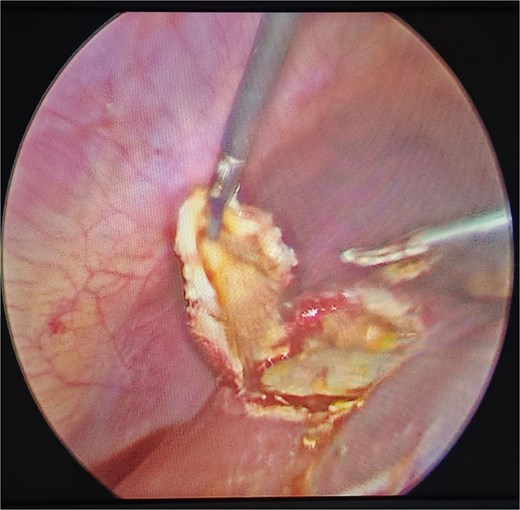

The treatment of cystic hydatid disease includes percutaneous drainage, medical therapy, and surgical intervention. While percutaneous aspiration-injection-reaspiration and albendazole therapy are viable options, surgery remains the preferred treatment for complicated cysts, offering the potential for complete cyst removal and full recovery [3, 6]. In our case, laparoscopic pericystectomy was successfully performed, leading to a favorable postoperative outcome (Figs 2–4).

Laparoscopic view of hepatic hydatid lesion (white focus on the liver surface).